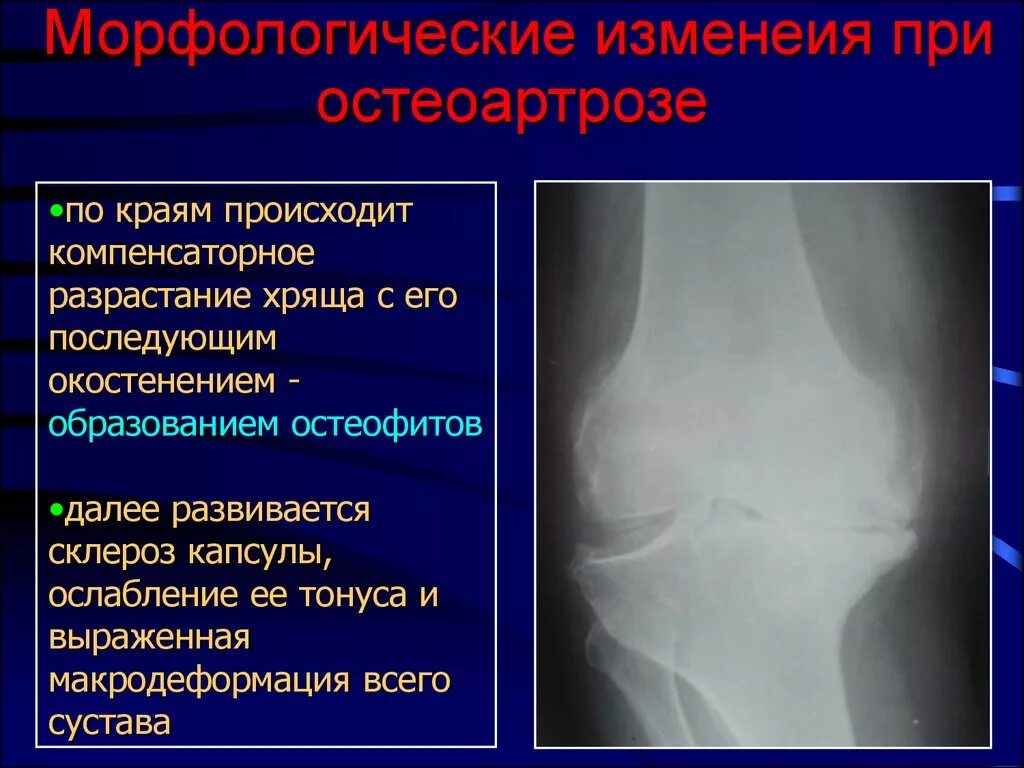

Остеофиты суставных краев